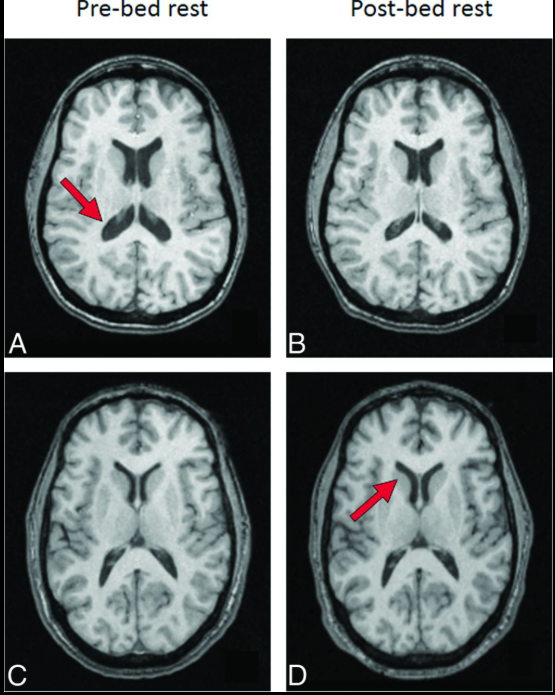

Trong nghiên cứu đăng trên tạp chí Proceedings of the National Academy of Sciences, các nhà khoa học đã công bố loạt ảnh chụp cộng hưởng từ (MRI) não của 26 phi hành gia, được thực hiện trước và sau các sứ mệnh ngoài Trái Đất. Khi đặt các hình ảnh này cạnh nhau, sự khác biệt trở nên rõ ràng.

Não bộ của phi hành gia có xu hướng dịch chuyển lên phía trên và ra sau bên trong hộp sọ. (Ảnh: PNAS)

Theo đó, sau thời gian sống và làm việc trên Trạm Không gian Quốc tế (ISS), não bộ của phi hành gia có xu hướng dịch chuyển lên phía trên và ra sau bên trong hộp sọ. Các rãnh não ở vùng đỉnh đầu bị nén lại, trong khi hệ thống khoang chứa dịch não tủy xuất hiện sự thay đổi về hình dạng.

Đáng chú ý, những biến đổi này không đồng đều trên toàn bộ não bộ. Ảnh MRI cho thấy các vùng liên quan đến cảm giác và vận động - những khu vực đóng vai trò quan trọng trong việc giữ thăng bằng và phối hợp cơ thể là nơi chịu ảnh hưởng rõ rệt nhất. Ngoài ra, các nhà khoa học còn ghi nhận những biến dạng cục bộ theo chiều ngang, mang tính phi tuyến và khác nhau giữa phần trên và phần dưới của não.

Để có cái nhìn toàn diện, nhóm nghiên cứu đã so sánh ảnh MRI của các phi hành gia với 24 người khỏe mạnh trên Trái Đất. Nhóm đối chứng này được đặt trong tư thế nằm nghiêng đầu xuống đất trong thời gian dài, một phương pháp thường dùng để mô phỏng môi trường vi trọng lực.

Kết quả cho thấy não bộ của nhóm người này cũng xuất hiện sự thay đổi về hình dạng và vị trí, khá giống với những gì quan sát được ở phi hành gia. Tuy nhiên, mức độ dịch chuyển lên trên của não không mạnh bằng, và các cấu trúc não nhìn chung vẫn ổn định hơn so với những người thực sự sống trong không gian.

Não bộ của người thường được đặt trong mô phỏng môi trường vi trọng lực mức độ dịch chuyển lên trên của não không mạnh bằng, và các cấu trúc não nhìn chung vẫn ổn định hơn so với những người thực sự sống trong không gian. (Ảnh: AJNR)